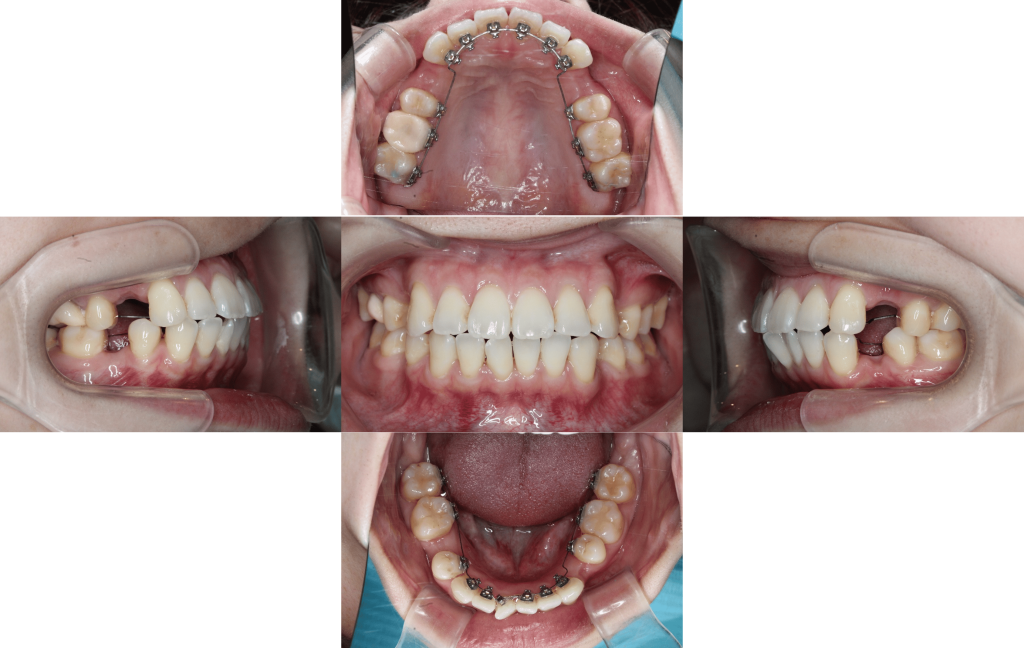

前歯のでっぱりで口が閉じずらい(治療期間約8か月/治療回数8回)

Before

After

年齢層

30代

性別

女性

主訴

・前歯のでっぱりで口が閉じずらい・舌癖を治したい・かみ合わせが悪い

治療費用

¥1,287,000(税込)

治療期間

約8か月

抜歯

上顎両側第一小臼歯、下顎右側第二小臼歯、下顎左側第一小臼歯

矯正の装置

マルチブラケット装置(裏側矯正)

副作用、リスク

歯肉退縮,歯根吸収,疼痛,咬合の違和感,装置の違和感,虫歯,歯肉炎